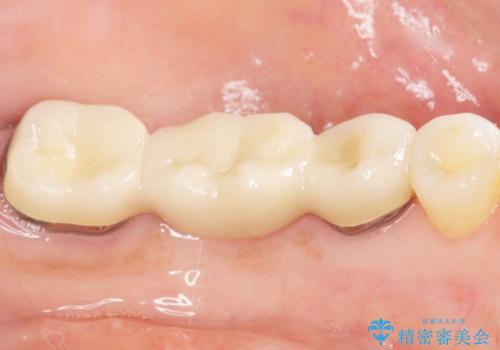

根管治療後、メタルボンドブリッジによる補綴治療を行いました。

自然な仕上がりと咬み心地に喜んで頂けました。

クラウンの種類:メタルボンドクラウン エコノミー